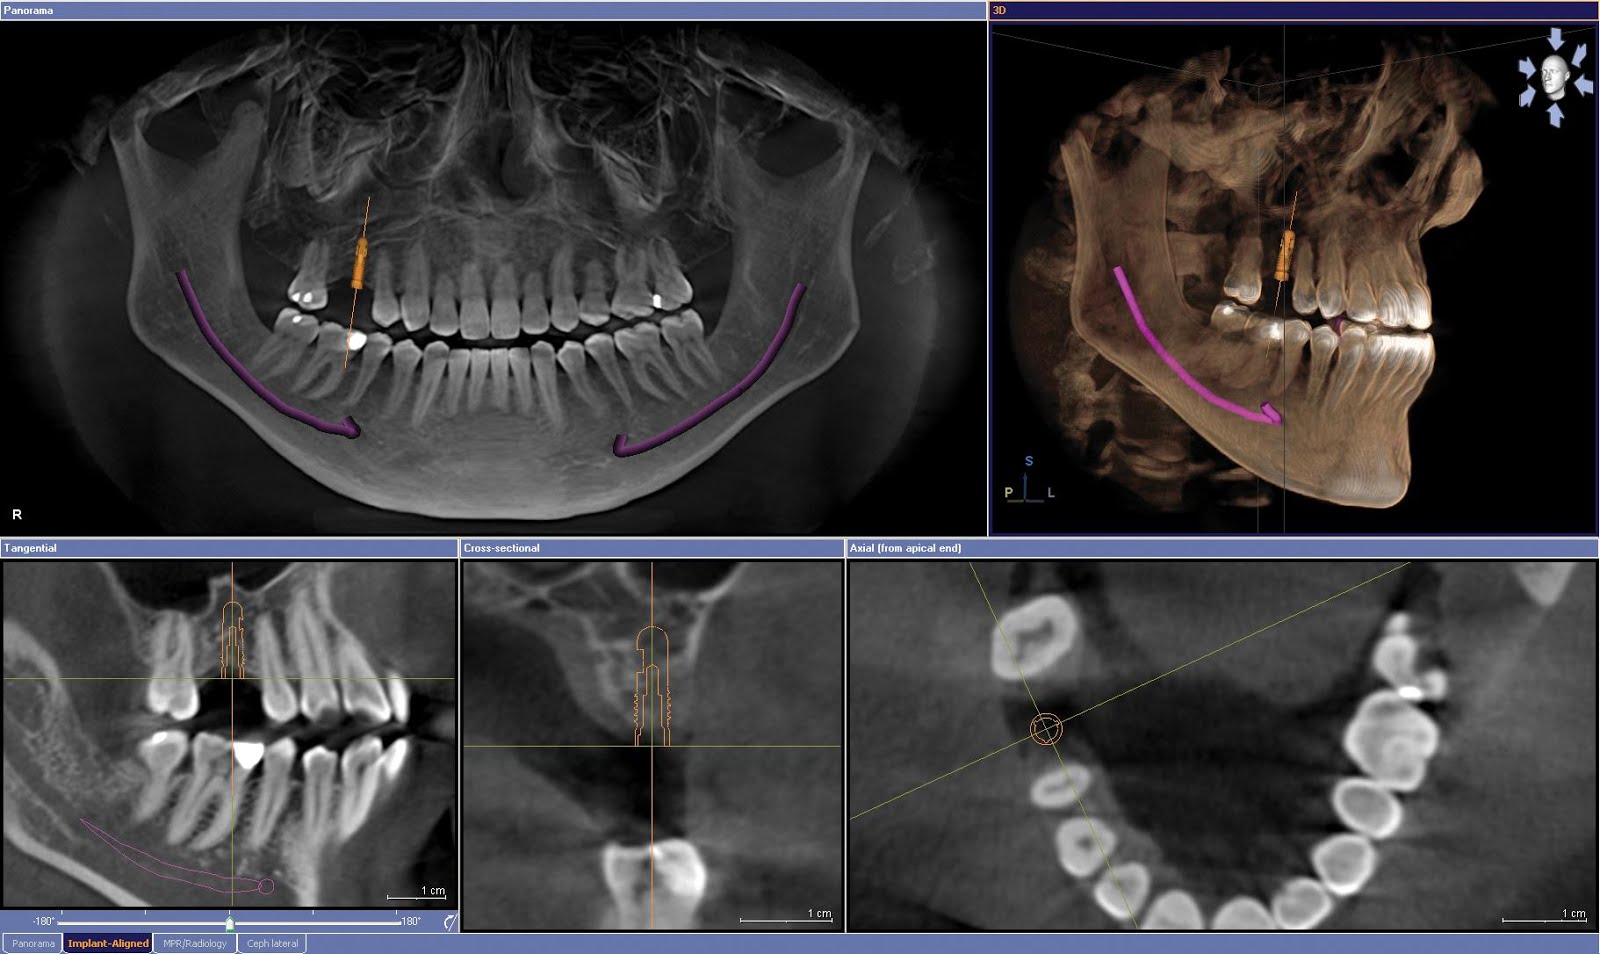

以植牙支撐活動牙

對於預算有限,或是骨頭條件不是那麼理想的病人來說,植2~6顆牙來做為全口假牙的支柱,穩定全口假牙,提高咬合力量,是相當不錯的選擇!